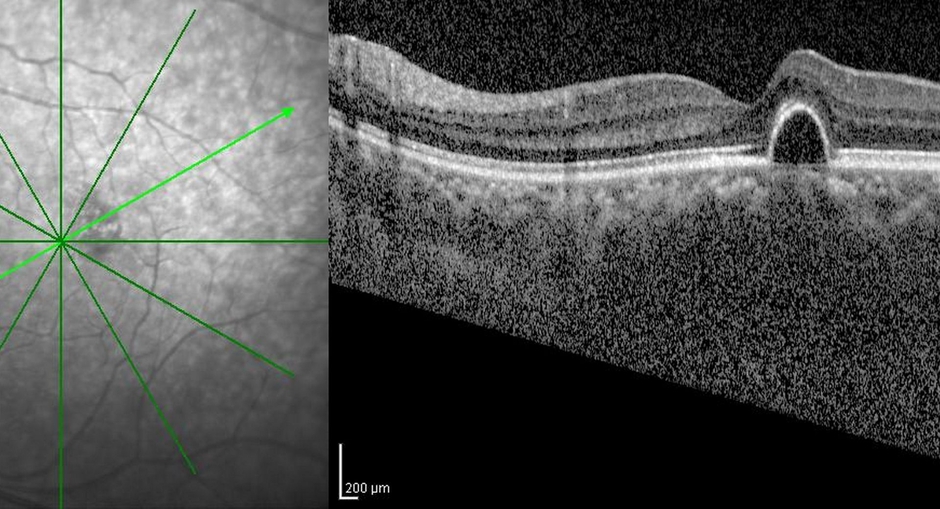

光干渉断層計(Optical Coherence Tomography: OCT)は、高解像度の断面画像を撮影するための新しい技術です。OCTイメージングは、超音波イメージングと似ていますが、音の代わりに光を使用します。OCTは、ミクロン単位の組織構造の断面画像を、その場でリアルタイムに得ることができます。OCTとカテーテルや内視鏡を併用することで、臓器の高解像度な腔内イメージングが可能です。OCTは、組織を採取して顕微鏡で検査する従来の病理組織学とは異なり、組織をその場でリアルタイムに撮影できるため、医療診断に適した画像技術です。OCTは、組織を採取して顕微鏡で検査する従来の病理組織検査とは異なり、その場でリアルタイムに組織の画像を得ることができるため、光生検のような使い方ができます。

また、遠視、近視、乱視、老眼などの視力障害の発生が増加していることから、OCTの需要が増加しています。さらに、ここ数年、ビタミンAの欠乏や事故の症例が大量に増加しています。OCTは、生きている眼の網膜と視神経の異なる層を可視化する優れた方法です。このような素晴らしい技術が発見される前は、患者さんが亡くなった後や眼球を摘出した場合にのみ、組織切片で眼球の様子を見ることができました。

世界の光コヒーレンス・トモグラフィー市場は、技術に基づいて、スペクトルドメインOCT(SD-OCT)とスウェプトソースOCTに分類されます。SD-OCTは、干渉縞パターンのスペクトル解析を用いて、後方散乱光の大きさと遅延に符号化された深さ方向の組織構造情報を提供する干渉計技術です。網膜や脈絡膜のイメージングでは、Swept Source光干渉断層計(OCT)が最新の技術です。スウェプトソースOCTでは、この技術で干渉パターンにフーリエ変換と呼ばれる処理を施すことで、すべての光のエコーを同時に測定することができます。

網膜や脈絡膜の障害が増加していることから、眼科の需要は将来的に増加すると予想されます。世界保健機関(WHO)によると、2019年には全世界で推定22億人が視覚障害を抱えており、そのうち10億人は予防可能だと言われています。そのため、眼科医がスクリーニングや診断の目的で光干渉断層計を使用することになっています。より高性能な機器の登場や、光コヒーレンス・トモグラフィーの精度や使いやすさなどの複数の利点により、眼科での使用がより魅力的になり、このセグメントの発展を後押ししています。